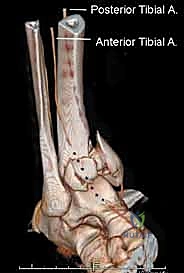

- التقييم العصبي الوعائي: وهو الأهم؛ يجب فحص النبض في شرايين القدم (Dorsalis Pedis & Posterior Tibial) للتأكد من عدم انقطاع التروية الدموية، وفحص الإحساس للتأكد من سلامة الأعصاب.

التشخيص الدقيق هو حجر الزاوية الذي يُبنى عليه التخطيط الجراحي. في عيادات الأستاذ الدكتور محمد هطيف، لا يتم الاكتفاء بالتشخيص المبدئي، بل يتم استخدام أحدث تقنيات التصوير الطبي:

كشفت الأبحاث المتقدمة (مثل أبحاث كول Cole وزملائه) والتي يعتمد عليها الدكتور هطيف، أن الأشعة المقطعية، وخاصة مع إعادة البناء ثلاثي الأبعاد (3D Reconstruction)، تسمح برسم خريطة دقيقة لكل قطعة عظمية مفتتة في السطح المفصلي (AO/OTA 43-C3).

تظهر الأشعة المقطعية النمط الثابت لتفتت البيلون والذي يتكون عادة من ثلاث قطع رئيسية:

* القطعة الأمامية الجانبية (Chaput fragment): متصلة بالرباط الظنبوبي الشظوي الأمامي.

* القطعة الخلفية (Volkmann fragment): متصلة بالرباط الظنبوبي الشظوي الخلفي.

* القطعة الأنسية (Medial Malleolus): متصلة بالرباط الدالي.

وفي الوسط، توجد منطقة "الانهيار المفصلي" (Die-punch fragment) التي تُدفع داخل العظم.

يستخدم الأستاذ الدكتور محمد هطيف هذه الخريطة المقطعية لتحديد مسار الشقوق الجراحية، واختيار أحجام وأنواع الشرائح المعدنية المطلوبة، وتحديد تسلسل إرجاع القطع العظمية قبل دخول غرفة العمليات.